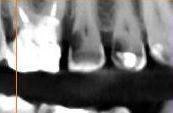

Доктор предлагает удалить, сначала пробовала - сверлила, сказала тонкие стенки, глубокий кариес ( вроде как под десну пошел) и не сделать коронку. Не могу сомневаться в квалификации доктора, вроде старается сохранить зубы до конца, рядом 1.6 развалившуюся которую в нескольких клиниках сразу на удаление посылали - реставрировала, 1.5 все хотели пульпитировать оставила живым залечив но здесь ни в какую хотя зуб выглядит и страшновато но не болит же. Снимки правда из кт 8 мес. назад - что есть если надо другую пропорцию - скину.